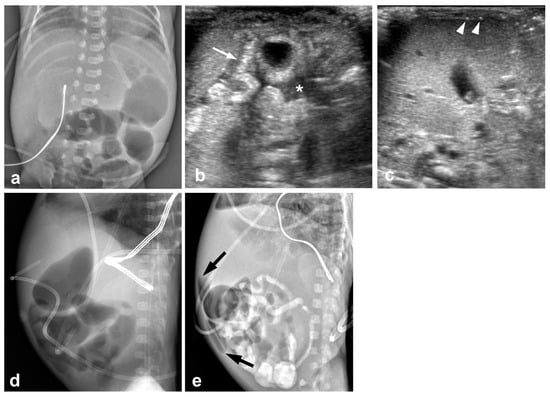

3.2. Imaging Findings

3.2.1. Abdominal Radiographs

3.2.2. Temporal Relation between Abdominal Radiographs and Bowel US